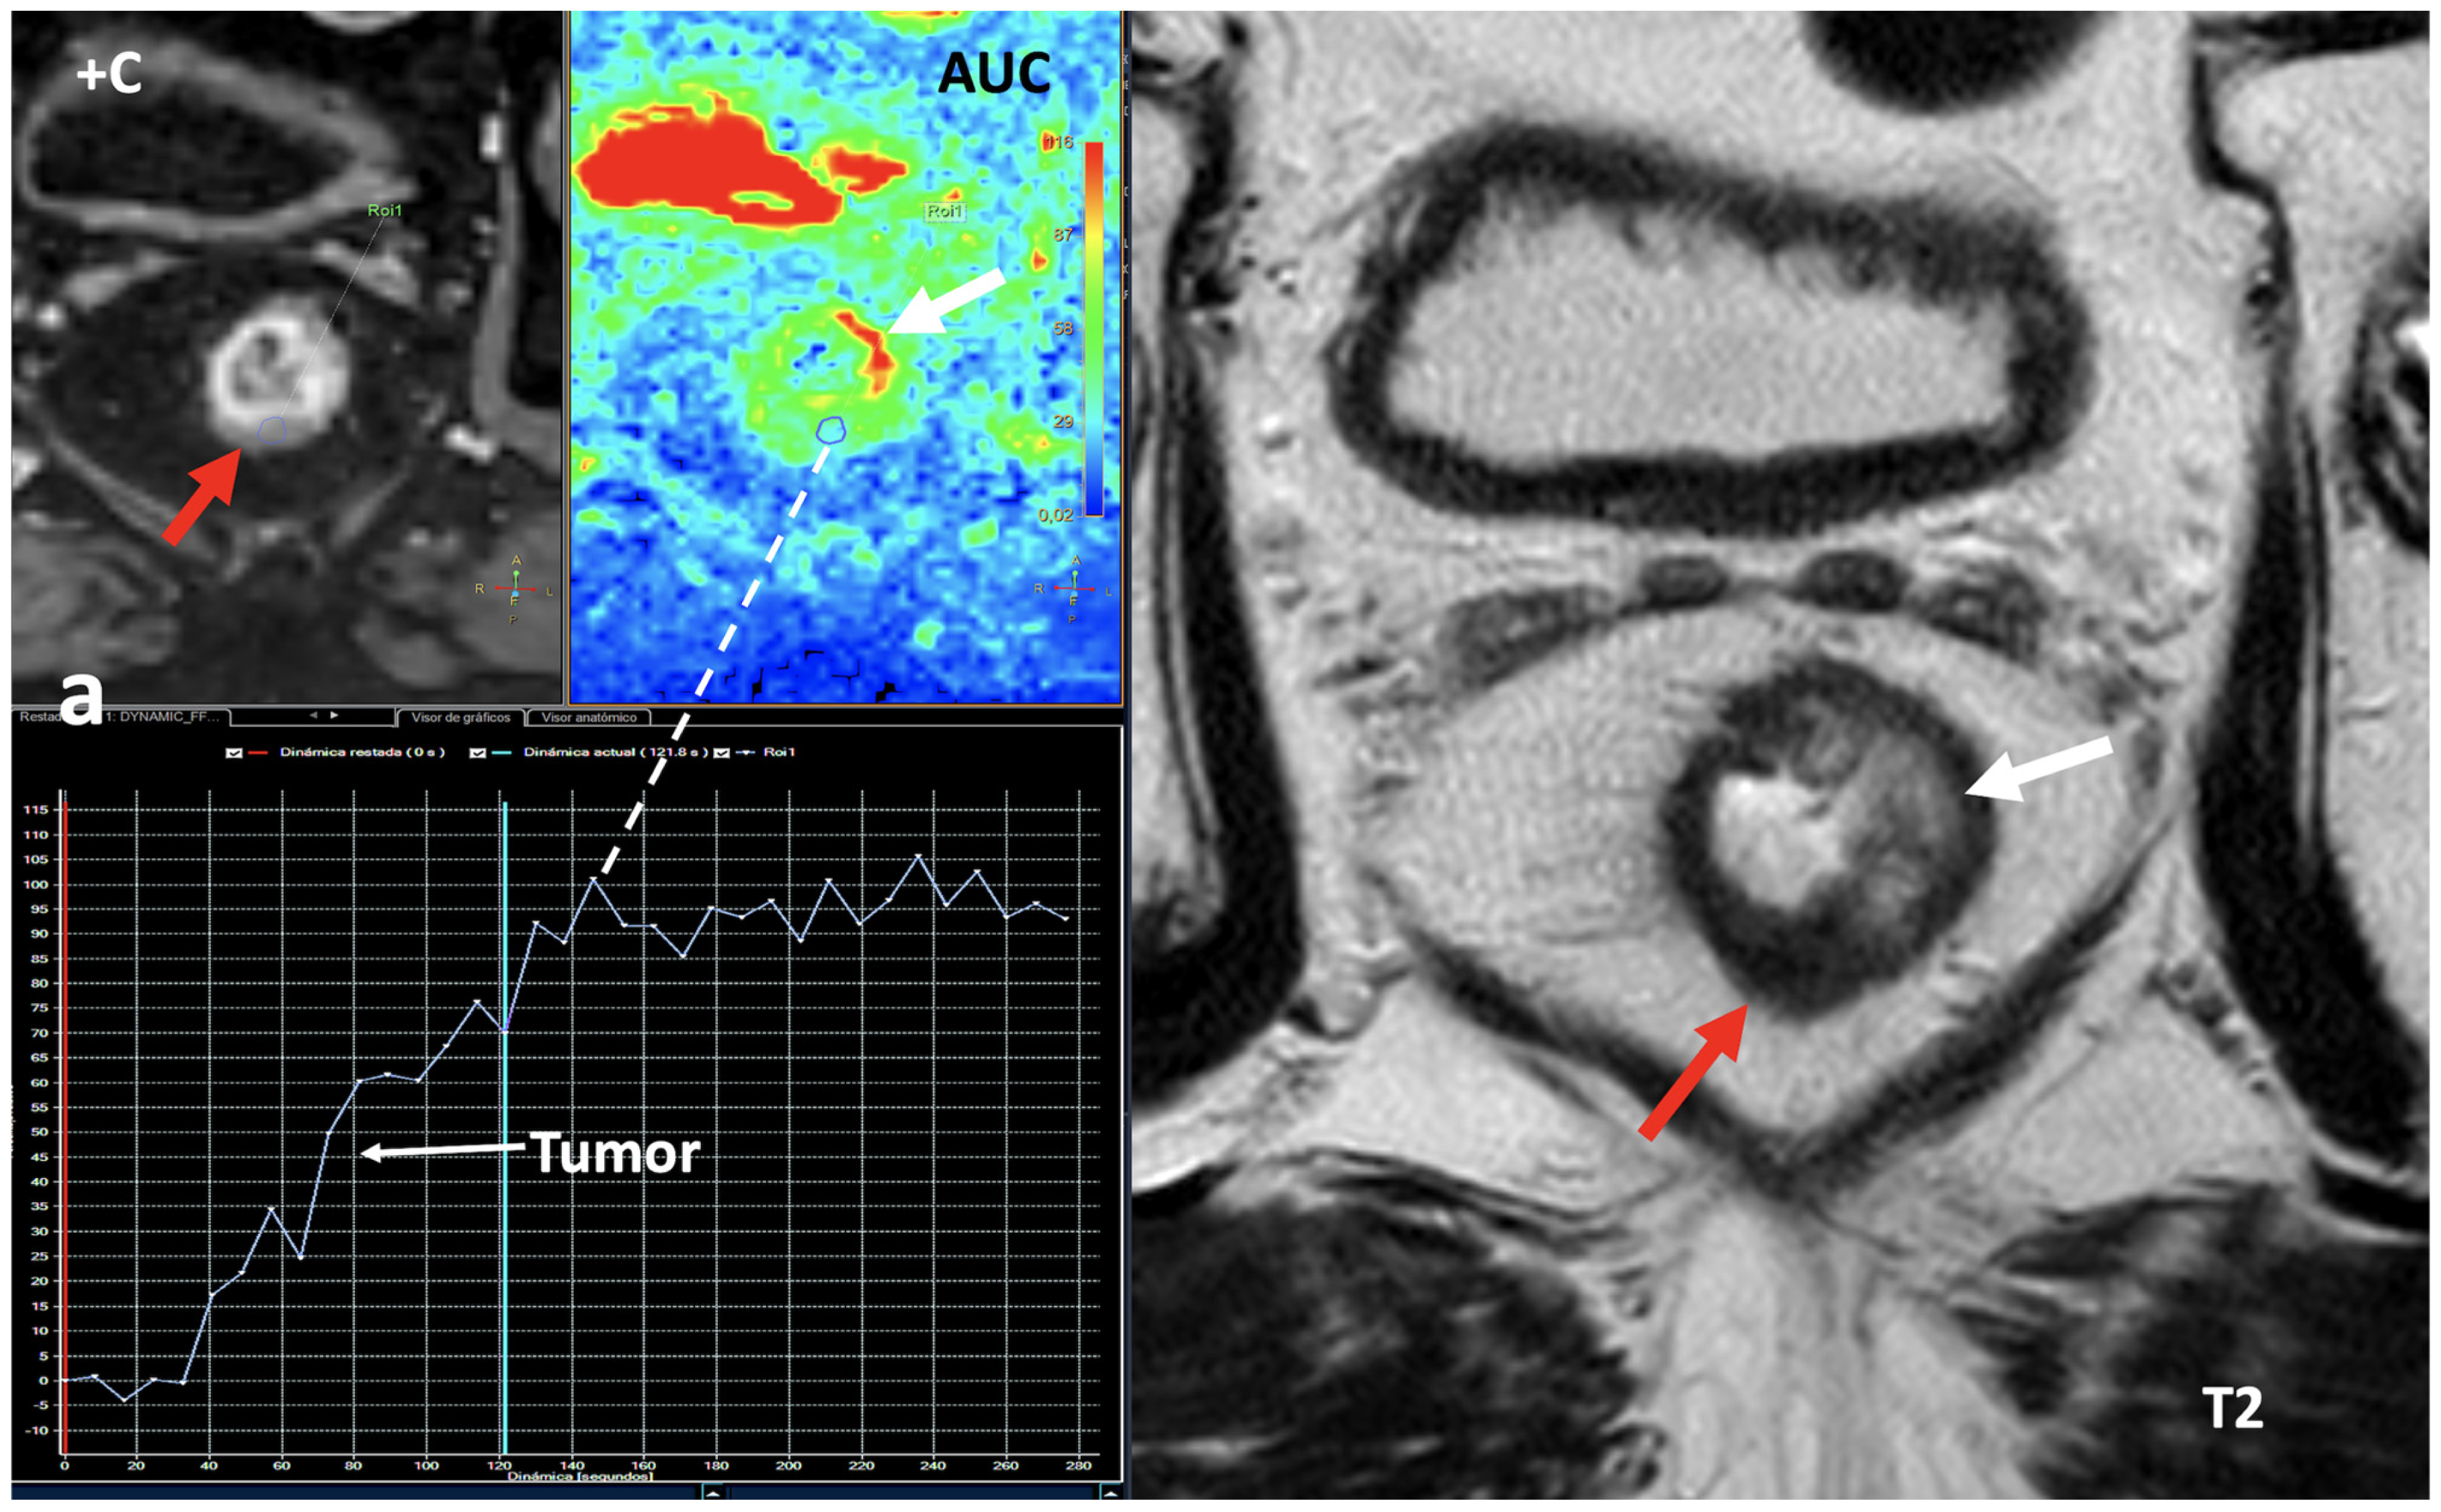

- Breast imaging. DECT seems to be a reliable tool for diagnosis and locoregional staging of breast cancer [36,37,38,39,40] (Figure 12). Klein et al. [37] found robust cut-off points for the differentiation of benign and malignant lesions (Zeff < 7.7, iodine content of <0.8 mg/mL). The DECT quantitative parameters may also be useful in predicting breast cancer invasiveness and histopathological and molecular subtypes of breast tumors. In the case of node staging, the similarity of quantitative DECT parameters between the primary lesion and axillary LNs may predict axillary metastasis in breast cancer [40,41].

- Currently, there is not a widely reported use of DECT in clinical management of prostate cancer. However, DECT imaging may facilitate the depiction of focal areas of increased enhancement in the periphery of the prostate in contrast-enhanced CT that may represent a clinically significant cancer and deserve further workup [42] (Figure 13).